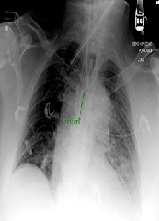

Combination of Unfractionated Heparin (UFH) and Triple Antiplatelet Therapy After Percutaneous Coronary Intervention (PCI) May Increase the Risk of Life Threatening Hemothorax in a Patient with Recent Rib Fracture

Javad Savoj, Asma Jamil, Syed Iftikhar, Rajesh Gulati*